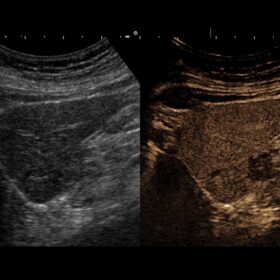

Radiology 2D, Color, Contrast and Elasto mode

- In radiology, a high-level of accuracy and reliability is necessary to ensure early detection, precise diagnosis, and to determine appropriate treatment. The ARIETTA V70* is equipped with advanced technologies that facilitate fast and accurate examinations. Such as Real-time Virtual Sonography (RVS), Real-Time Tissue Elastography and Shear Wave measurement.